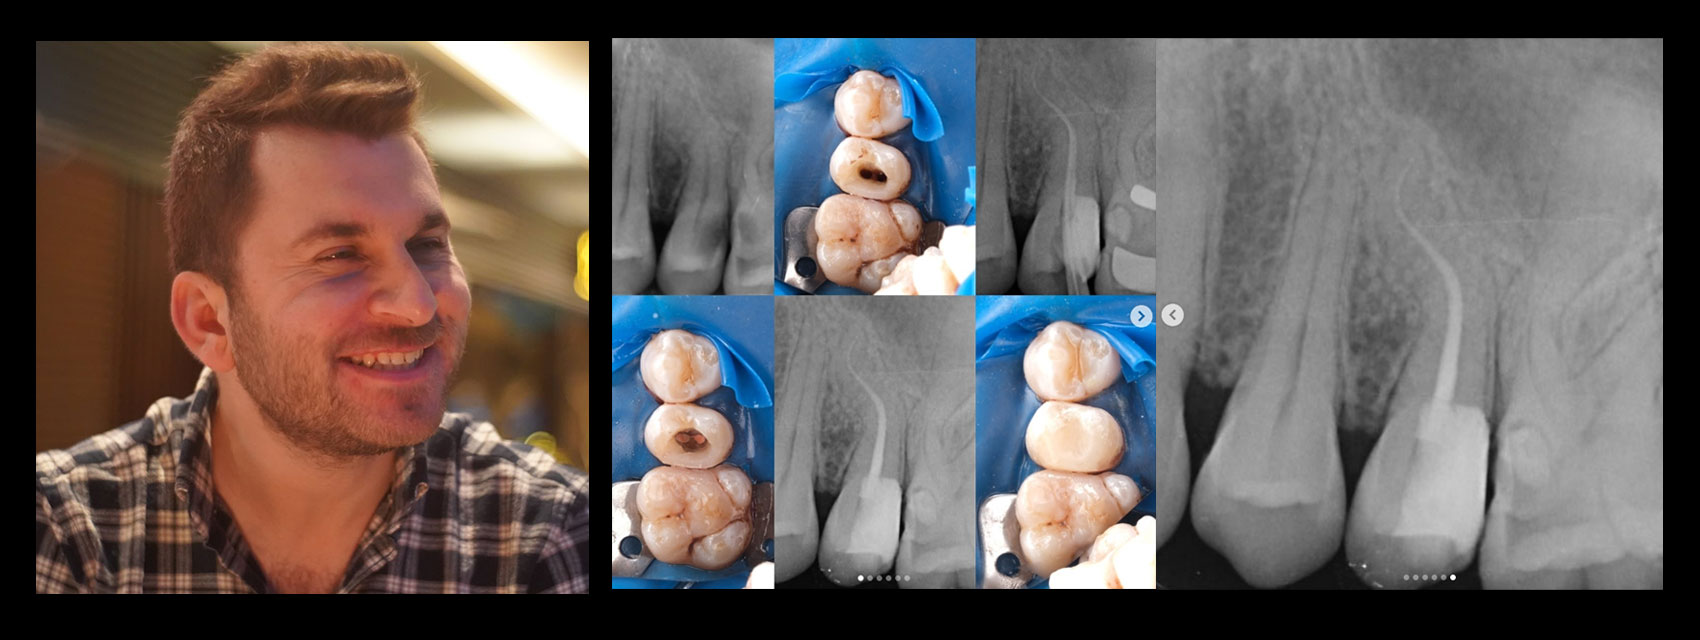

📌 Tooth #25 – Root Canal Treatment Case

📍 Diagnosis:

• The patient presented to the clinic with spontaneous pain, and a diagnosis of irreversible pulpitis was made, indicating the need for root canal treatment.

• The roots exhibit two curvatures, and although there are two canals, they converge at a single apical foramen.

🔧 Treatment Steps:

1. A rubber dam was placed.

2. A pre-endo build-up was performed and the cavity was converted to Class I.

3. The canals were prepared without using any hand files, using only the Perfect Super System Advanced Kit, in the following sequence:

10/.07 → 10/.04 → 17/.05 → 25/.04

Copious irrigation and ultrasonic activation were used throughout preparation.

4. A working length radiograph was taken with gutta-percha cones to confirm canal length.

5. The treatment was completed in a single visit, using a bioceramic root canal sealer.